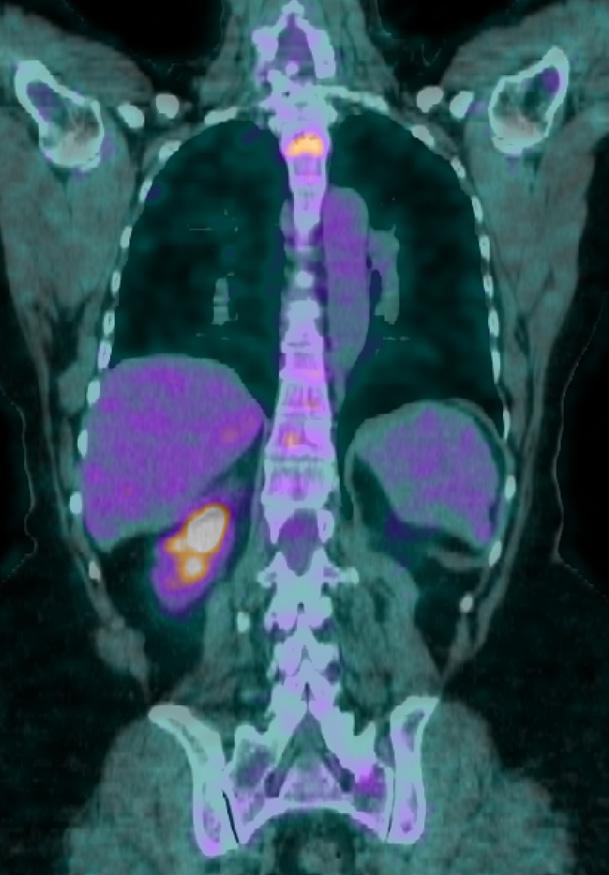

Nel 2022-2024, la paziente riceve chemioterapia secondo schema TEX (epirubicina, docetaxel, capecitabina) per 4 cicli, per poi proseguire con docetaxel + capecitabina fino a Gennaio 2024 (21 cicli totali). Durante il trattamento si osserva risposta parziale in tutte le sedi note di malattia, con successiva progressione cerebrale documentata da RMN nel Febbraio 2024. Nel Febbraio 2024, a seguito della progressione encefalica evidenziata da RMN – con la comparsa di multiple lesioni cerebellari, parietali e occipitali sinistre (figura 1) – viene avviato il trattamento con trastuzumab deruxtecan (T-DXd) alla dose di 5,4 mg/kg ogni 21 giorni. La scelta terapeutica si basa sulla confermata espressione HER2 low del tumore primitivo, identificata all’esordio e successivamente confermata tramite biopsia della malattia metastatica. Fin dalle prime somministrazioni, la paziente mostra una buona tolleranza al trattamento. Dopo i primi due cicli, non vengono riferiti effetti collaterali rilevanti, e il quadro clinico si mantiene stabile. Con il progredire della terapia, dopo quattro cicli, si osserva l’insorgenza di una sindrome mano-piede di grado 1-2, gestita con terapia sintomatica senza necessità di modifiche posologiche.

Alla prima valutazione strumentale dopo sei cicli, la TC documenta una stabilità dei secondarismi encefalici e ossei, accompagnata da una buona risposta epatica, suggerendo un’efficacia precoce del trattamento. Parallelamente, la paziente mantiene un buon perfor-

La stabilità encefalica persiste anche dopo dieci cicli, con una riduzione parziale delle lesioni epatiche, segno di un beneficio clinico duraturo. Dopo dodici cicli, il trattamento continua a essere ben tollerato: non emergono eventi avversi significativi, e la funzione cardiaca risulta conservata, con una frazione di eiezione (FE) del 67%.

Alla quattordicesima somministrazione, la rivalutazione mediante TC mostra una sostanziale stabilità della malattia epatica e ossea (figura 2). Tuttavia, la RMN encefalica evidenzia un incremento dimensionale della lesione cerebellare sinistra, associata a edema perilesionale (figura 3). Pur in assenza di sintomi neurologici, si decide di avviare una terapia corticosteroidea a scalare per il controllo dell’edema.

Figura 1. A livello emisferico cerebellare a destra lesione puntiforme di circa 1 mm.

In sede paravermiana superiore a destra lesione di circa 9 mm.